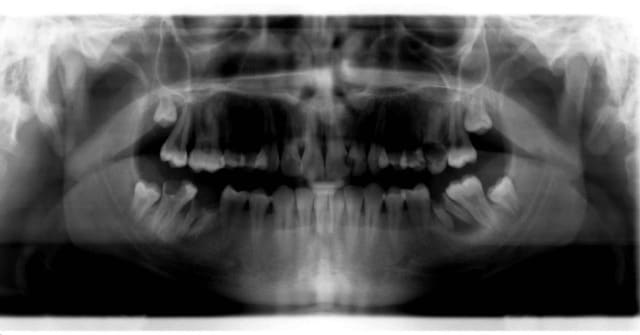

Mon grand jeu avec ce genre d'urgence, c'est de deviner la dent qui fait mal en regardant la pano avant de voir le patient.

au pif, je mise tout sur la 36.

Le patient arrive, en fait il a mal à droite surtout au froid.

Zut, c'est la pulpo de la 47 qu'il va falloir faire.

Quand j'ai vu ça je n'ai pas pu resister : "vous savez pour le detartrage, il faut déjà se brosser les dents. Mais il ne faut pas tenir la brosse par les poils. Car là c'est franchement sale. et le detartrage c'est franchement un détail à ce stade".

J'ai fait sa pulpo sur la 47 aprés avoir traversé le capuchon gingival qui faisait office de composite occluso distal.

Le gars a 18 ans, une bouche bien crade, et j'ai retrouver de la plaque dentaire sur mon ecarteur photo...